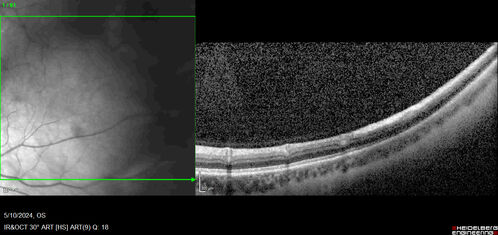

Myelinated Nerve Fiber Layer - Peripheral

43 year old man with floaters